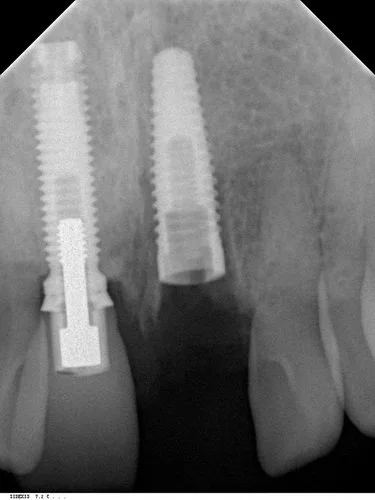

Tooth 21 was removed and due to excellent primary stability being achievable, with good interproximal bone height (Tarnow 1998) a Replace Select implant was placed immediately, with 40+ Ncm of torque being achieved. This allowed for placement of an immediate provisional restoration. The patient’s natural crown was used along with a titanium provisional abutment to construct a pleasing provisional restoration.